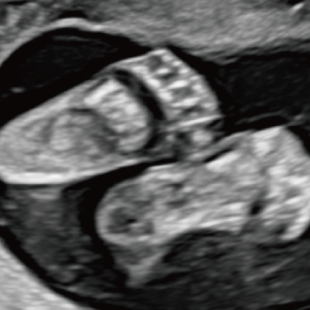

妊娠中期になると、胎児の体や内臓の構造がよりはっきりと確認できるようになります。 中期スクリーニングでは、頭部、顔面、頸部、胸部、腹部、心臓、手足、外性器、臍帯や胎盤など、全身をくまなく観察し、形態の状態を詳しく確認します。この頃に染色体数の変化を疑わせる所見が確認される事もあります。

胎児ドックの様子_中期_頭 胎児ドックの様子_中期_顔面 胎児ドックの様子_中期_心臓 胎児ドックの様子_中期_腹部 胎児ドックの様子_中期_足 胎児ドックの様子_中期_4D